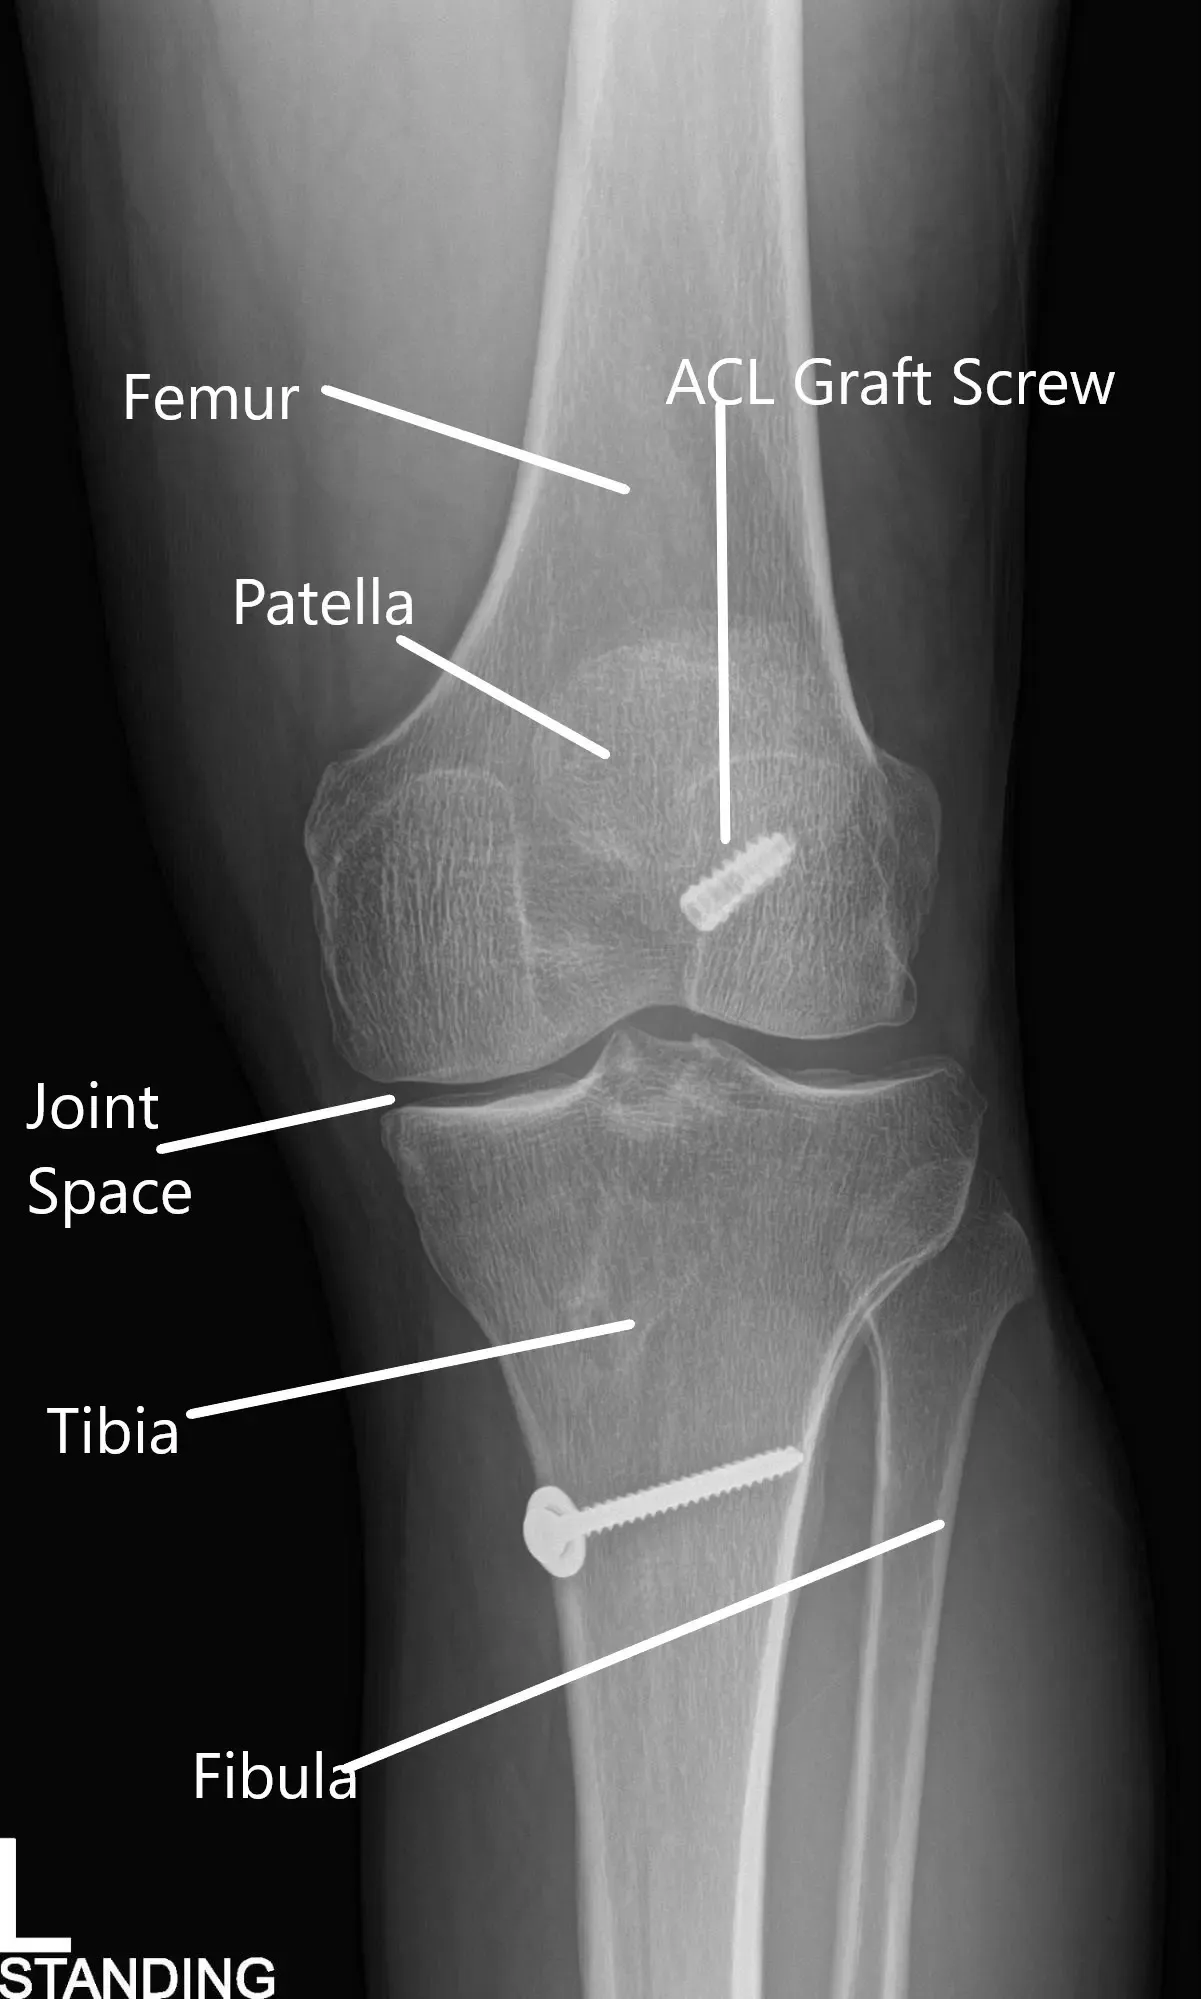

Radiografía de la rodilla izquierda en vistas AP y lateral.

Una radiografía de la quilla izquierda sugirió un estrechamiento moderado del compartimento articular medial y un estado tras la reconstrucción del LCA.